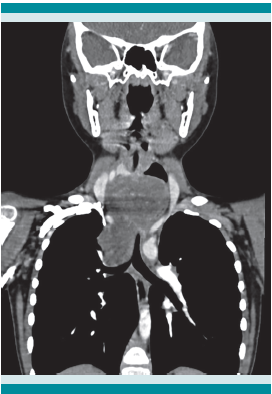

Las radiografías postero-anterior y lateral de tórax evidenciaron ensanchamiento mediastinal, de predominio superior hacia la derecha y desplazamiento con compresión anterior de la luz de la tráquea, secundario al ensanchamiento del espacio retro-traqueal, respectivamente. (Figura 1) La tomografía computada de cuello y mediastino simple, con contraste, reportó una lesión neoformativa del espacio prevertebral (mediastinal posterior y superior) que comprimía y desplazaba anteriormente la tráquea y el esófago, con calcificaciones lineales escasas y estructuras vasculares del cuello desplazadas lateralmente. Figuras 2 y 3

Después de ingresar al INP, la radiografía de tórax y la tomografía lograron delimitar la ubicación de la neoplasia en el segmento posterior del mediastino, de acuerdo con la taxonomía de Carter y sus colaboradores.3Figura 4